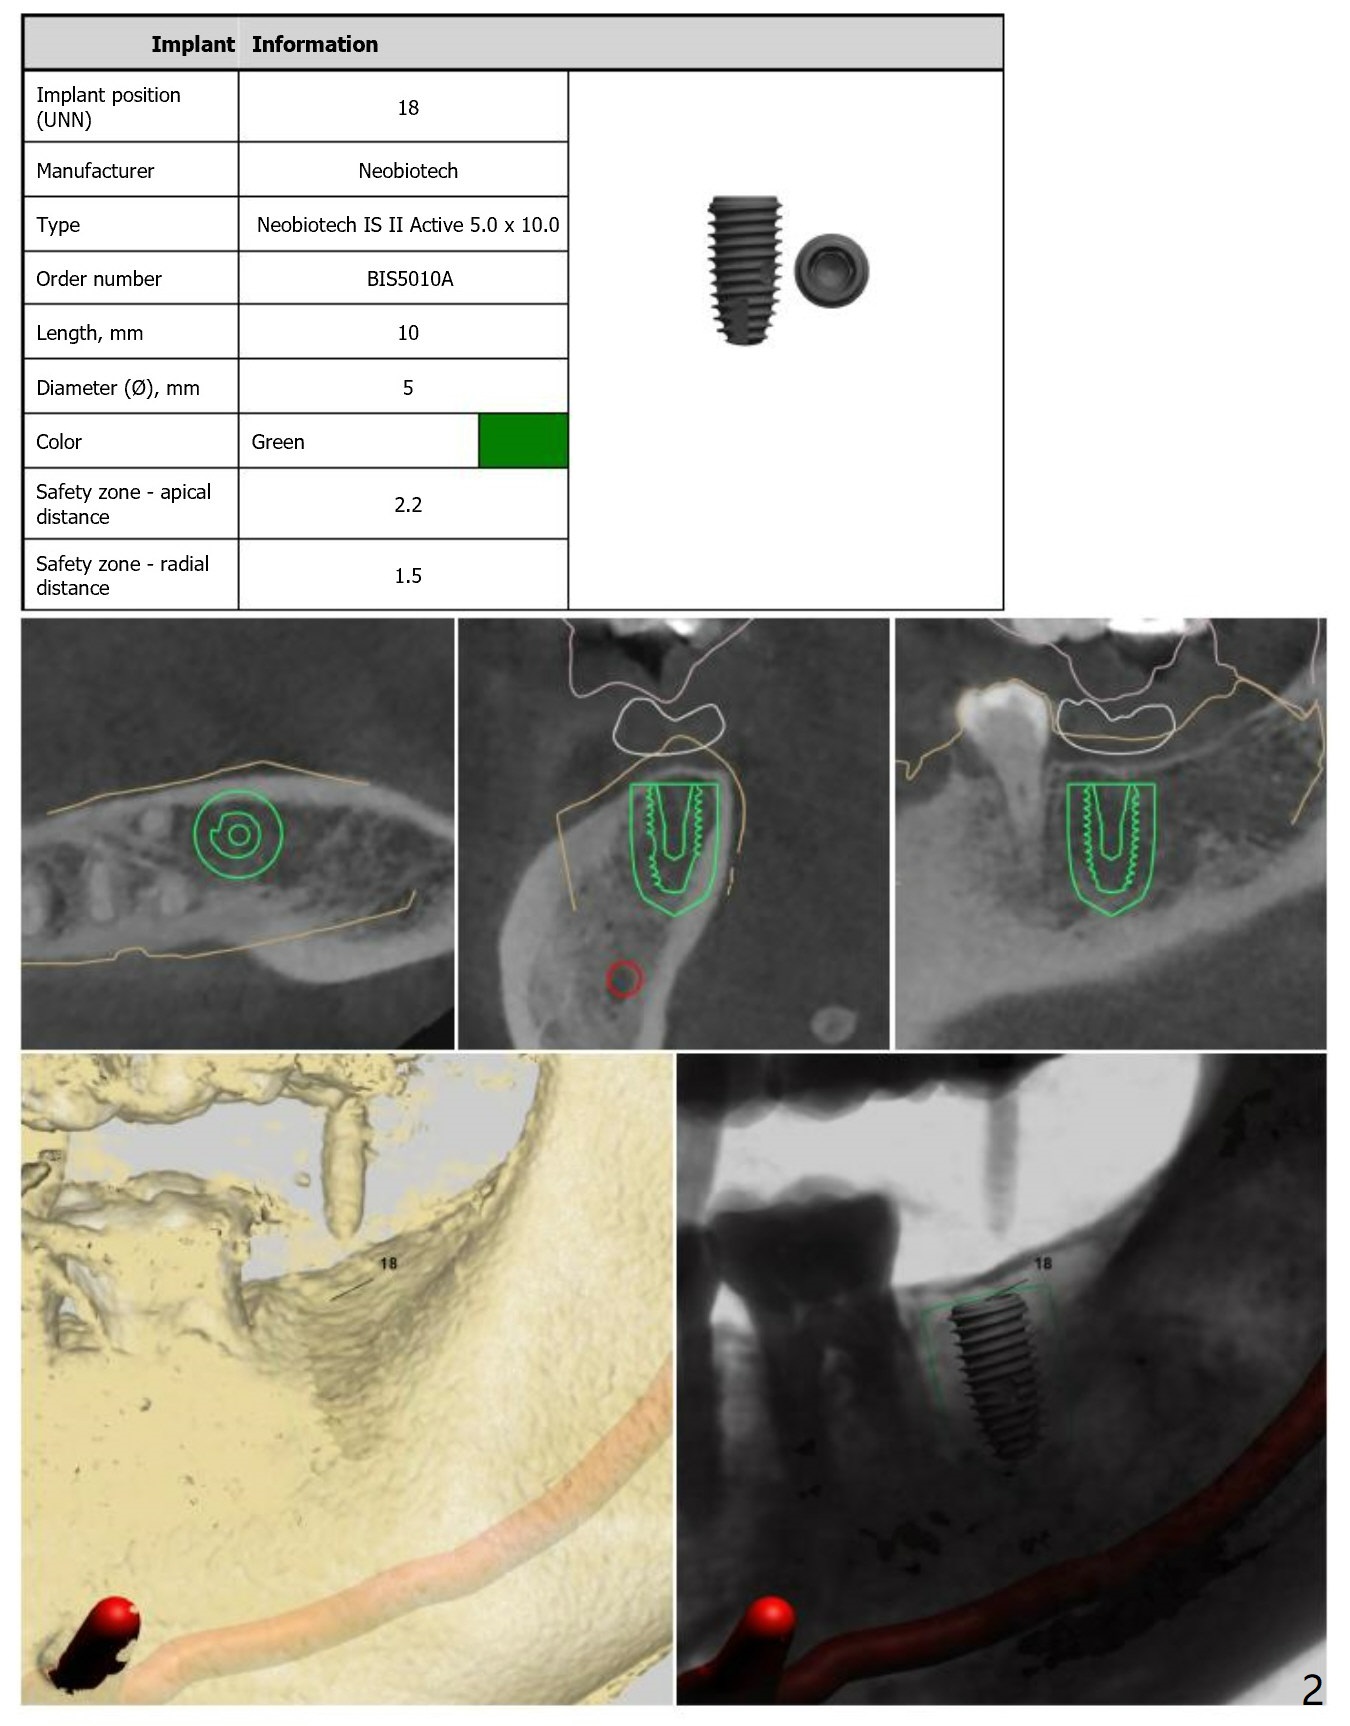

Guide Design

Return to Lower Molar Immediate Implant, Armaments, Surgery